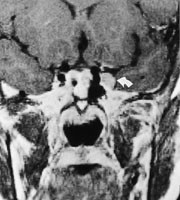

Langsomt progredierende oculomotoriusparese med pupillaffeksjon kan være forårsaket av nevrinom, som er isointens på T1- og T2-vektede MR-bilder og viser kraftig signalopptak etter intravenøs injeksjon av gadoliniumkontrast (fig 3).